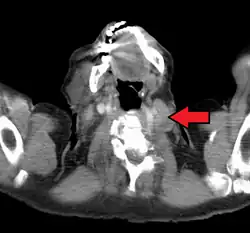

The supraclavicular lymph nodes can be felt in the supraclavicular fossa, shown here.